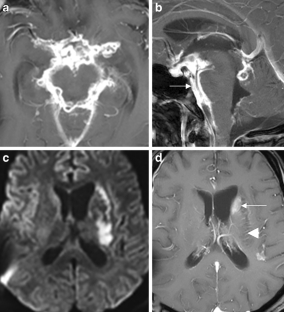

The CNS TB can be manifested (1) diffuse as tuberculous meningitis (TBM), (2) localized as tuberculoma or (3) tuberculous abscess or (4) in extradural and intradural spinal infections. Information on clinical presentation, underlying pathology and the distinguishing features is demonstrated. The TBM is further described, which may lead to cranial nerve palsy, hydrocephalus and infarction due to associated arteritis of the basal perforators. The differential diagnoses are vast and include other infections, such as bacterial, viral or fungal meningoencephalitis, malignant causes or systemic inflammation with CNS. Complicating factors of diagnosis and treatment are HIV coinfection, multi-drug resistance and TB-associated immune reconstitution inflammatory syndrome (IRIS).